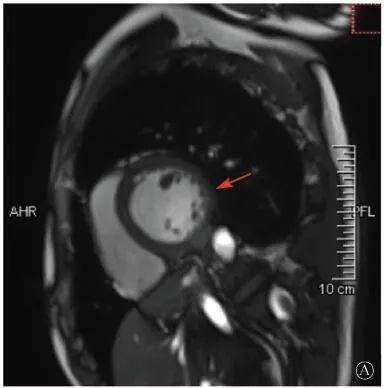

案例介紹:患者男性,20歲,因?yàn)?quot;胸痛4個(gè)月,加重1月余"于2019年7月10日入院?;颊?019年4月無(wú)明顯誘因出現(xiàn)心前區(qū)隱痛,VAS 3分,無(wú)放射,無(wú)胸悶、憋氣、活動(dòng)后氣短,每月發(fā)作1~2次,未在意。同年5月體檢發(fā)現(xiàn),肌酸激酶(CK)2928 U/L、肌酸激酶MB質(zhì)量(CK-MB)46 U/L、心肌肌鈣蛋白I(cTnI)0.055 ng/ml。6月初,患者"感冒"后出現(xiàn)心前區(qū)疼痛加重,為過(guò)電樣疼痛,VAS 5分,無(wú)放射,持續(xù)約30~60 min可好轉(zhuǎn),胸痛每周約發(fā)作2次,否認(rèn)呼吸困難、胸悶、心悸,否認(rèn)活動(dòng)耐量下降。6月8日,患者就診于外院查血生化:CK 1 215→1433 U/L,CK-MB 47 U/L,cTnI 30.17→31.79 ng/L;血脂(-);抗核抗體譜(-);超聲心動(dòng)圖:左室增大,左室舒張末內(nèi)徑57 mm,左室射血分?jǐn)?shù)39%,輕度二尖瓣關(guān)閉不全;磁共振心肌灌注延遲動(dòng)態(tài)成像(圖1):左室稍增大,收縮功能稍減低;基底部至心尖部左室下壁及側(cè)壁、心尖部左室前壁心外膜下心肌纖維化,考慮非缺血性心肌病;肌電圖:肌源性損害(偏慢性)。診斷"多發(fā)性肌炎、心肌損傷",予患者倍他樂(lè)克緩釋片23.75 mg/d、培哚普利0.5 mg/d、螺內(nèi)酯20 mg/d口服,患者未再出現(xiàn)心前區(qū)疼痛,但步行1 km左右會(huì)出現(xiàn)氣短、乏力。為進(jìn)一步明確心力衰竭病因收入我院。患者上高中起出現(xiàn)體育課等劇烈活動(dòng)后雙下肢明顯乏力,不能耐受1 km長(zhǎng)跑類運(yùn)動(dòng),日常體力活動(dòng)不受影響,否認(rèn)肌肉酸痛等不適。此次發(fā)病以來(lái),一般情況尚可,否認(rèn)尿量減少,體重?zé)o明顯變化。既往史:否認(rèn)高血壓、冠心病、糖尿病病史。個(gè)人史:否認(rèn)特殊毒物藥物接觸史,無(wú)煙酒嗜好?;橛?、家族史:未婚未育,否認(rèn)家族類似病史,否認(rèn)遺傳病史。入院查體:脈搏69次/min,血壓112/70 mmHg,指氧(自然狀態(tài))98%,體質(zhì)指數(shù)21.1 kg/m2;無(wú)皮疹;雙肺呼吸音清;心律齊,未聞及雜音;肝脾不大;雙側(cè)腓腸肌肥大,肌肉無(wú)壓痛;四肢肌力Ⅴ級(jí)、肌張力正常。雙下肢不腫。輔助檢查:入室床旁超聲心動(dòng)圖提示左室壁運(yùn)動(dòng)普遍減低,心尖部、左室下后壁為著,肌小梁增多。

左室壁較廣泛心外膜下延遲強(qiáng)化,可見(jiàn)左室下后壁肌小梁增多(箭頭所示)

圖1 患者外院磁共振心肌灌注延遲動(dòng)態(tài)成像